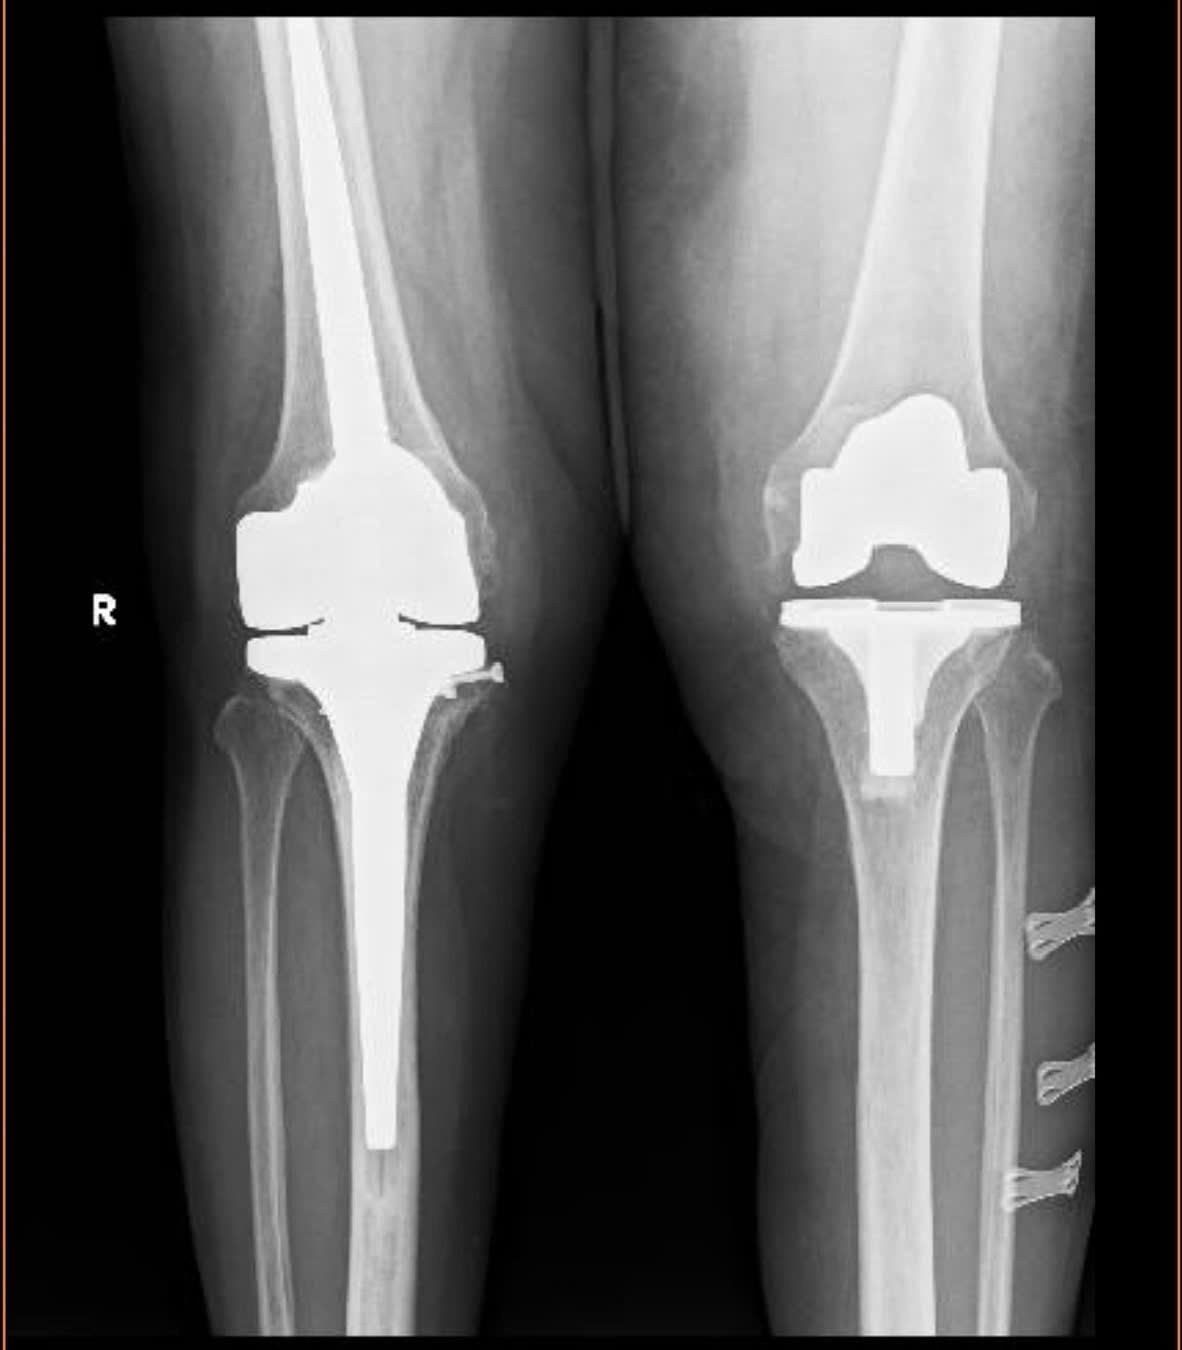

Khớp gối của bệnh nhân X. trước và sau khi phẫu thuật.

Bệnh nhân là bà Hồ Thị X. (69 tuổi, trú xã Chân Mây - Lăng Cô, TP Huế). Bệnh nhân X. nhập viện tháng 6/2025 trong tình trạng đau nhức dữ dội, hai khớp gối bị biến dạng nghiêm trọng. Trong đó, gối phải vẹo 40 độ, gối trái vẹo ngoài, khiến mỗi bước đi đều cong vẹo và mất vững.

Ngày 16/6, các bác sĩ tiến hành thay khớp gối bản lề bên phải, giúp trục chân được chỉnh thẳng, hết đau, dáng đi ổn định hơn. Đến tháng 8, bệnh nhân tiếp tục được thay khớp gối toàn phần bên trái. Sau thời gian ngắn tập phục hồi chức năng, bà X. đã có thể tự đi lại độc lập, không cần dụng cụ hỗ trợ. Sau đó, bà X. đã được xuất viện trong niềm vui của gia đình cùng đội ngũ y bác sĩ.

Đại diện Bệnh viện Trung ương Huế cho biết, thay khớp gối toàn phần là kỹ thuật thường quy tại đơn vị. Tuy nhiên, với những ca biến dạng nặng, mất chức năng dây chằng hoặc thiếu hụt xương nhiều, các loại khớp nhân tạo thông thường không còn phù hợp.

Lần đầu tiên ứng dụng tại bệnh viện, khớp gối bản lề trở thành giải pháp tối ưu cho các ca bệnh khó, vừa khắc phục biến dạng, vừa phục hồi vận động, mang lại hy vọng cho nhiều bệnh nhân vốn được coi là không thể điều trị bằng phương pháp thường quy.

TS. BS Nguyễn Thái Bảo - Trưởng khoa Phẫu thuật Khớp – Y học thể thao, Phó Giám đốc Trung tâm Chấn thương Chỉnh hình – Phẫu thuật Tạo hình, người trực tiếp thực hiện ca mổ, cho biết, khớp gối bản lề là loại khớp đặc biệt, đòi hỏi chuyên môn cao trong cả khâu chỉ định lẫn phẫu thuật. Đây là lựa chọn tối ưu cho những ca bệnh phức tạp, giúp bệnh nhân lấy lại sự vững chắc và khả năng vận động.